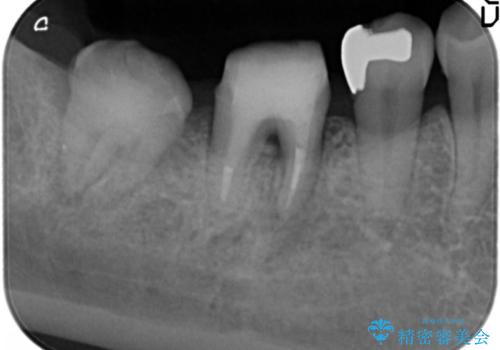

- 他院で根管治療を受け銀歯をかぶせるところまで行ったが、直後より腫れ・痛みが引かず当院へ相談、来院されました。

X線写真検査より根管充填の行われていない根管、視診より歯肉からの排膿路を認め、急性根尖性歯周炎の治療として根管再治療を計画します。

治療途中、マイクロスコープでも根管が追えないほど狭く細くなった根管へと変性しており根管の拡大形成が難しい状況でした。

CTを撮影し少しづつ丁寧に根管を探索することで無事根管再治療を行い、症状がなくなりました。